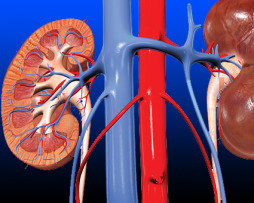

Renal Physiology

Duration : 8 hours 14 mins